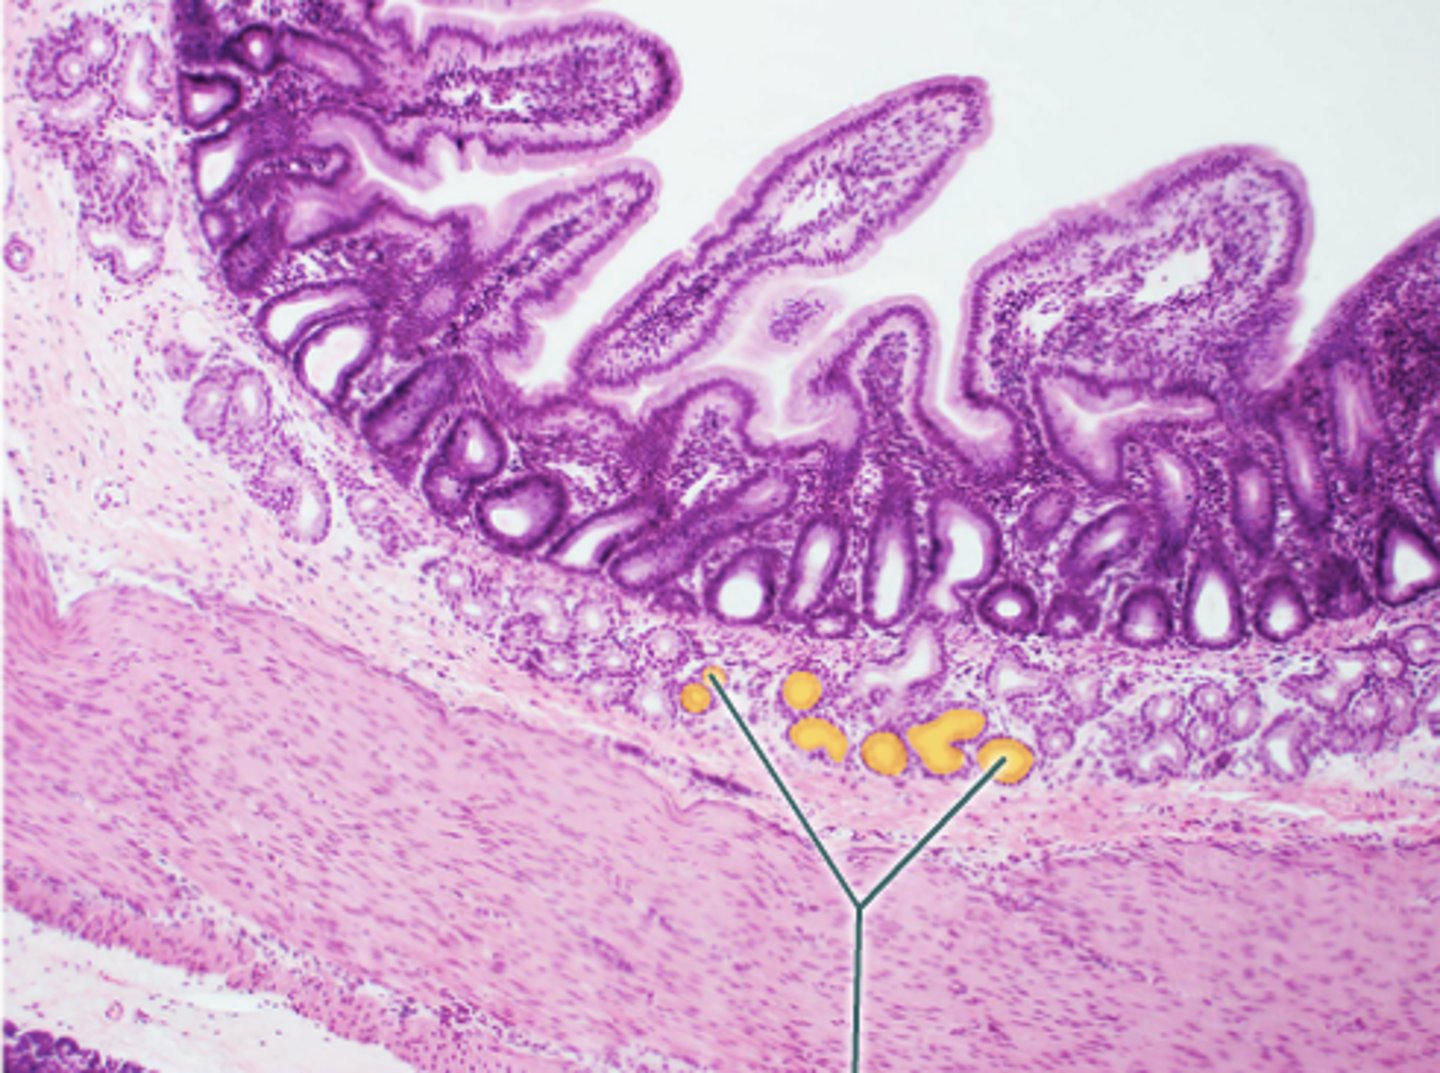

duodenum

What is this?

Brunner's glands

What are the glands in the duodenum?